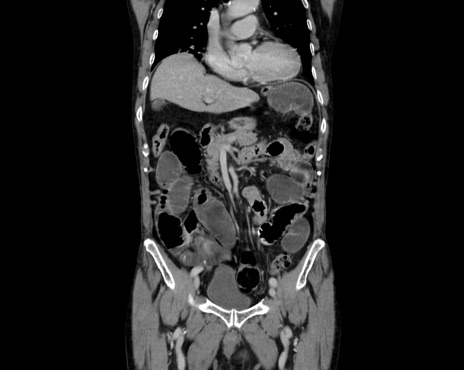

症例26(冠状断像)

【症例】80歳代男性

【主訴】嘔吐

【現病歴】昨晩2回嘔吐あり、今朝になっても嘔吐あり。来院。

【既往歴】胃潰瘍

【身体所見】意識清明、BT 37.6℃、BP 166/95mmHg、HR 100bpm、SpO2 97%、腹部:平坦・軟、腸蠕動音聴取良好、圧痛なし。

【データ】WBC 21900、CRP 1.4